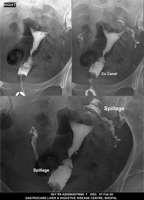

Section: HSG

Total: 49 Cases

All Categories BaM Enteroclysis Loopogram BaE Fistulogram Urethrogram HSG